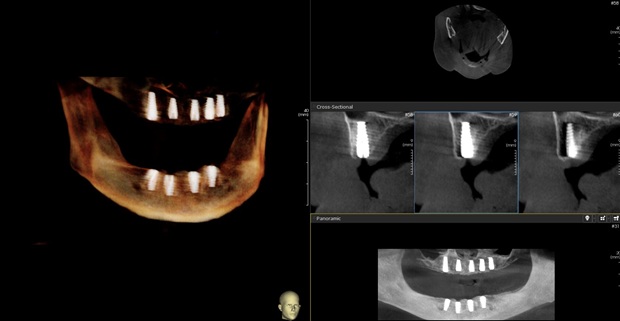

Replacing the top or bottom arch of teeth with standard dental implants would require an implant for each tooth. Alternatively, All-on-X uses spaced implants to replace the top or bottom row of teeth. The treatment works even if the patient has no teeth. As explained in this article by the American Academy of Implant Dentistry, the implants, usually a minimum of four, support the entire arch of replacement teeth. Also, this treatment does not require bone grafting. The implants will fuse with the existing bone and become part of the jaw. Because some of the implants are set at an angle, they are longer and offer more support.

All-on-X implant treatment is similar to getting regular implants. However, the procedure and recovery time are faster. First, the dentist will take impressions and X-rays and send those to a lab. At a subsequent appointment, our team will use a local anesthetic to numb the patient and may have to remove any remaining damaged teeth. Then, the dentist will insert a predetermined number of screws into their appropriate places in the upper and lower jaw. These titanium anchors will help support the artificial teeth throughout the mouth.